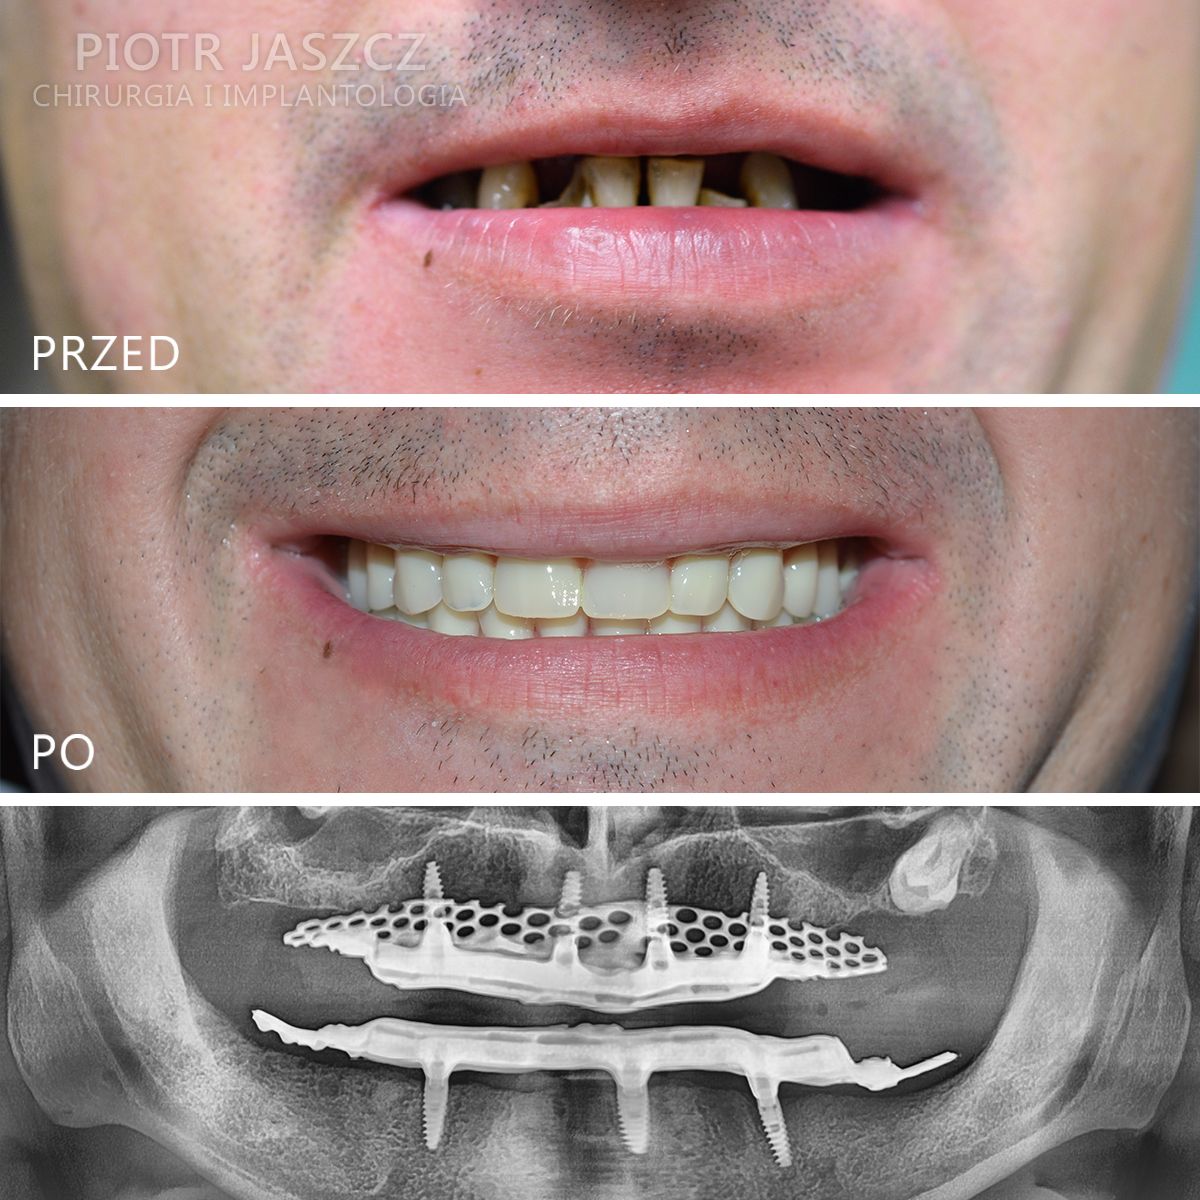

Specjalizuje się głównie w skomplikowanych odbudowach implantologicznych pacjentów bezzębnych oraz w zaawansowanych regeneracjach kostnych w leczeniu implantologicznym metodami przeszczepów kości własnej, jak również w przeszczepach tkanek miękkich w celu regeneracji dziąsła przy zębach lub przy implantach.

Wykonuje zabiegi odtworzenia zębów w 24h, polegające na usunięciu wszystkich zębów w szczęce lub żuchwie, wszczepieniu implantów metodą All-on-4 lub All-on-6 oraz oddaniu mostów na wszczepionych implantach w 24h. Metamorfozy szczęki w 24h.